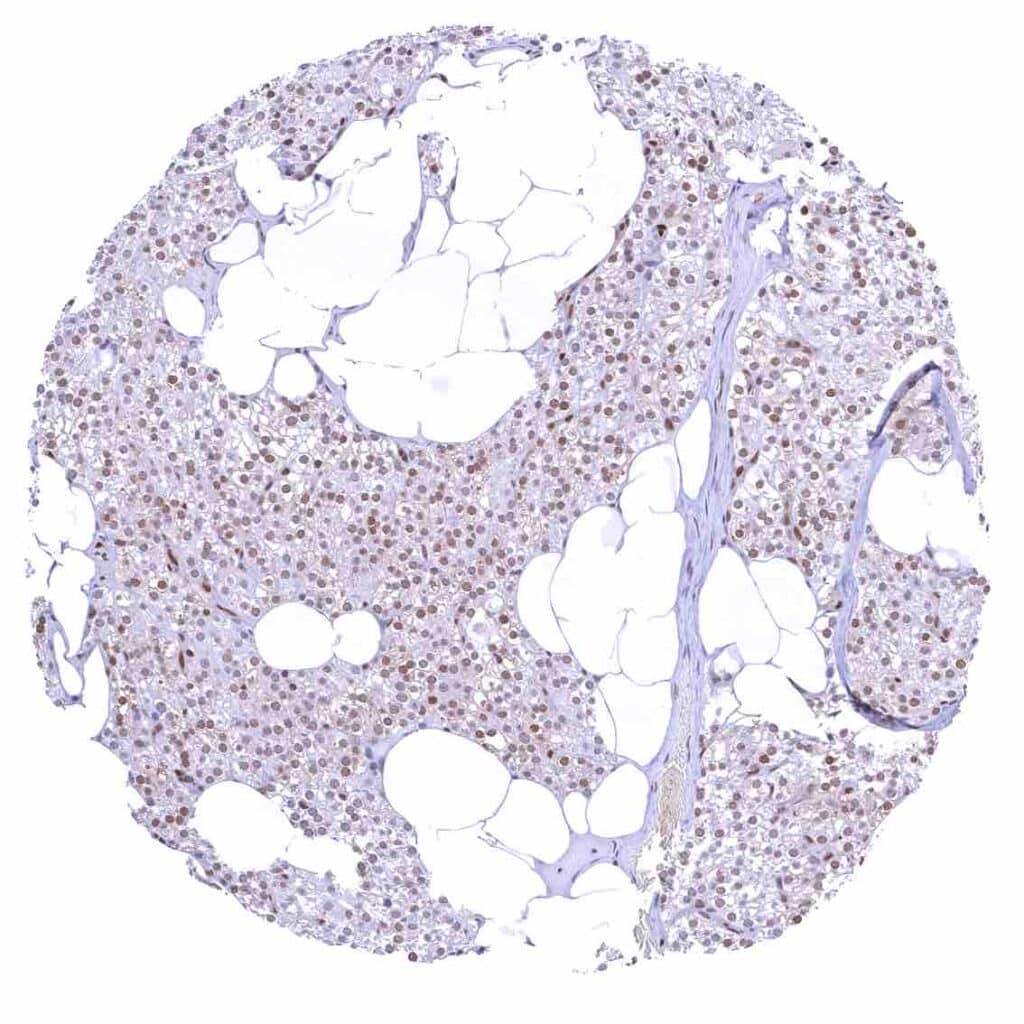

Adrenal gland – Distinct nuclear p27 positivity of a large fraction of cells.